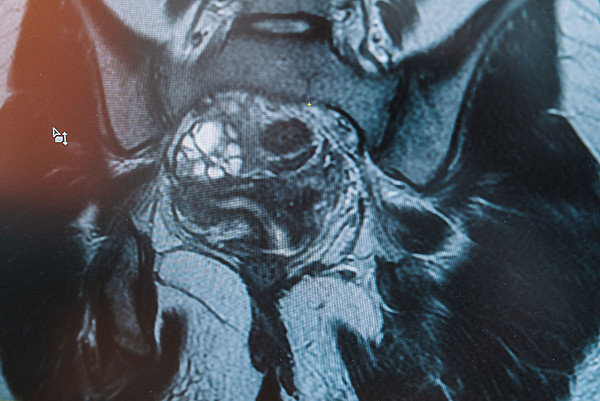

Врачи Кировской детской областной больницы сохранили репродуктивное здоровье девочки с редкой патологией матки